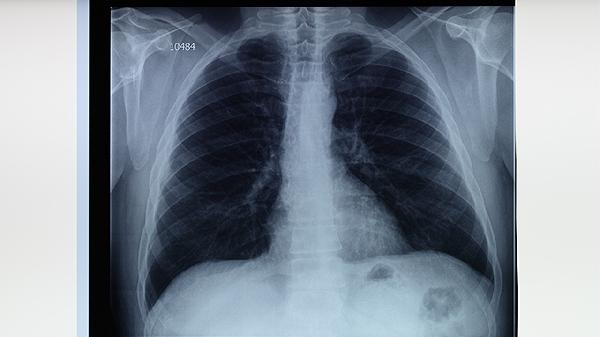

高危人群每1-2年进行胸部X线检查,接触者需做结核菌素试验或γ-干扰素释放试验。出现持续咳嗽、低热、盗汗等症状时应及时就诊,早期发现可通过异烟肼片、利福平胶囊等药物进行预防性治疗。